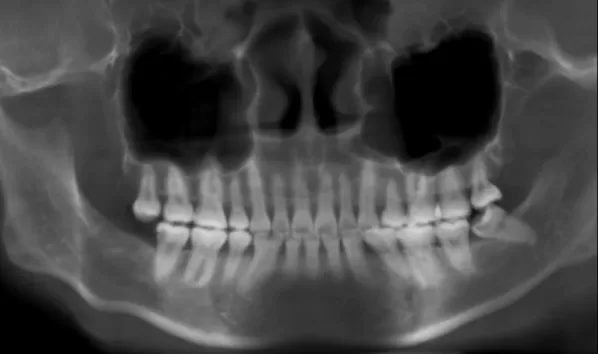

Rayons X avant le traitement

[Radiographie panoramique/Céphalogramme latéral]